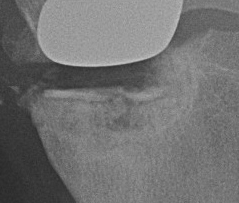

Patient 1

Patient 2